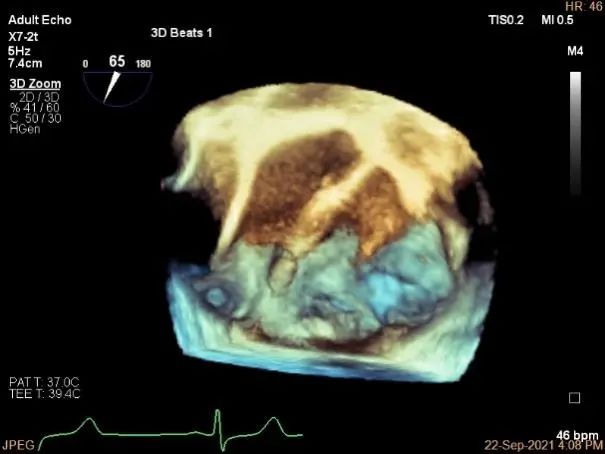

3D:P1区脱垂并腱索断裂,部分AC受累,Width:11.4mm

3D-color:重度MR,4级

3d确认夹子位置在P1区

3d-color确认残余分流情况

计算前叶捕获长度9mm,后叶捕获长度7mm。

夹子夹闭后,未见明确残余分流